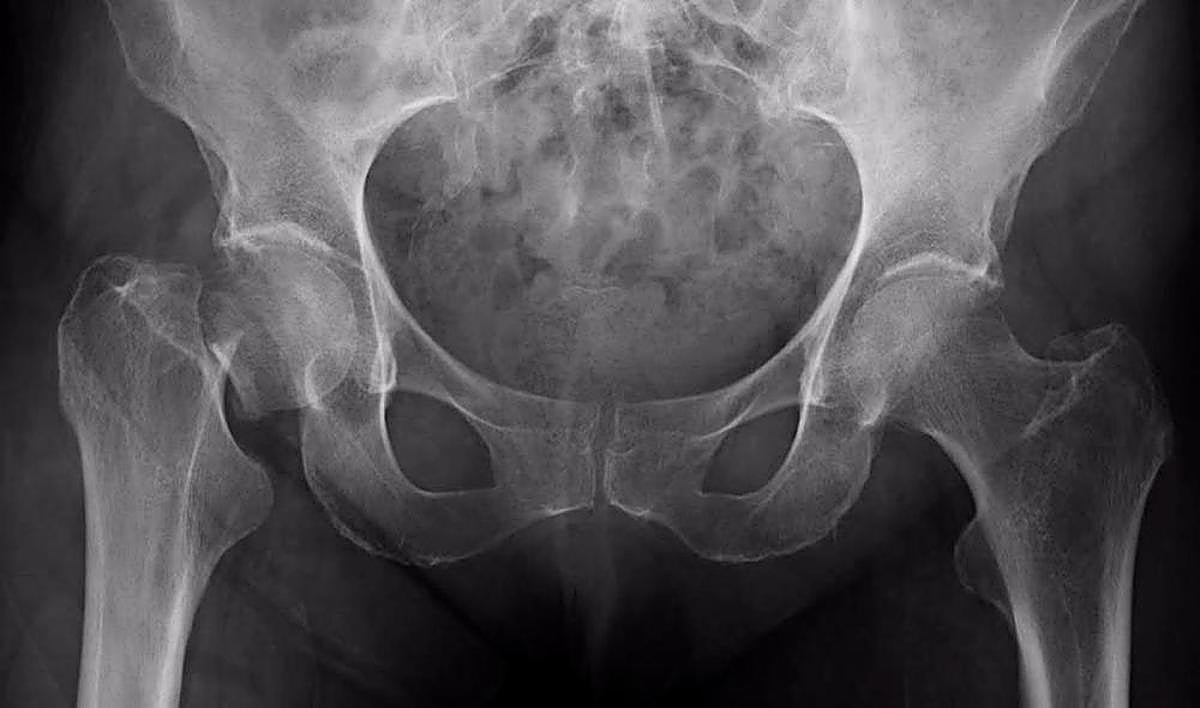

Radiografía de una cadera E.P.

Un nuevo estudio dirigido por investigadores de la Universidad de Hong Kong ha revelado que la fractura osteoporótica de cadera, que ya es un problema peligroso y debilitante para los hombres y mujeres de edad avanzada de todo el mundo, está a punto de convertirse en un problema de salud pública mundial mucho más grave a medida que la población envejece y es más frágil, al estimar que se duplicarán en todo el planeta en 2050.

La carga de las fracturas de cadera va a crecer, pero el tratamiento posterior a la fractura sigue siendo inadecuado en muchos países. Mientras tanto, la incidencia de la fractura de cadera en personas mayores de 85 años (los “mayores”) sigue siendo más del doble que en otros grupos de edad, mientras que el tratamiento postfractura en esta población es generalmente conservador.